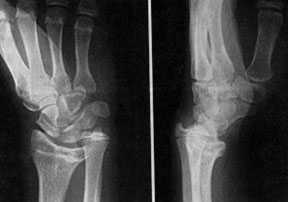

Рентгенограмма кисти с деформацией Маделунга

Маделунга болезнь (синоним: деформация Маделунга, хронический подвывих кисти)локальная физарная дисплазия, характеризующаяся укорочением лучевой кости и вывихом (подвывихом) локтевой кости, что внешне проявляется выстоянном головки локтевой кости и смещением кисти в ладонную сторону.

Костная деформация обусловливает своеобразную штыкообразную деформацию лучезапястного сустава, которая развивается вследствие преждевременного закрытия дистальной эпифизарной зоны роста лучевой кости, что ведет к прогрессирующему ее укорочению. Чаще поражается одна конечность. Иногда болезнь Маделунга сочетается с диспластическим сколиозом.

У девочек болезнь Маделунга встречается в 34 раза чаще, чем у мальчиков. Первые ее признаки обычно появляются в возрасте 9-12 лет, во время бурного роста длинных трубчатых костей. Нередко болезнь Маделунга необоснованно связывают с возможными травмами сустава, перенесенными воспалительными процессами. Вначале отмечают косметический дефект, ограничение движений кисти в тыльную и локтевую стороны. Деформация с возрастом увеличивается, появляются боли и ощущение усталости при движениях, обусловленные инконгруэнтностью суставных поверхностей.

Диагноз устанавливают на основании характерных клинических и рентгенологических проявлений. При рентгенологическом исследовании выявляют относительное укорочение лучевой кости на 45 см и скошенность суставной поверхности дистального эпифиза лучевой кости в ладонную и локтевую сторону, что создает впечатление подвывиха кисти (костей запястья). Полулунная кость как бы нависает над ладонным краем эпифиза лучевой кости. Высота дистального эпифиза по лучевой стороне значительно превосходит его высоту по локтевой стороне, а раннее закрытие эпифизарной ростковой зоны по локтевой и ладонной стороне создает ладонный и локтевой наклон суставной поверхности. Отмечают изменение расположения проксимального ряда костей запястья, они образуют клин, на вершине которого располагается полулунная кость. Головка локтевой кости находится в положении вывиха (в дистальном направлении) и смещена в тыльном направлении относительно лучезапястного сустава. Обычно расположена на уровне основания пястных костей.

Лучевая кость укорочена и дугообразно искривлена, имеется диастаз между дистальными отделами костей предплечья ("luxatio ulnae") с вклинением туда проксимального ряда костей запястья. Кисть смещена в ладонную сторону.